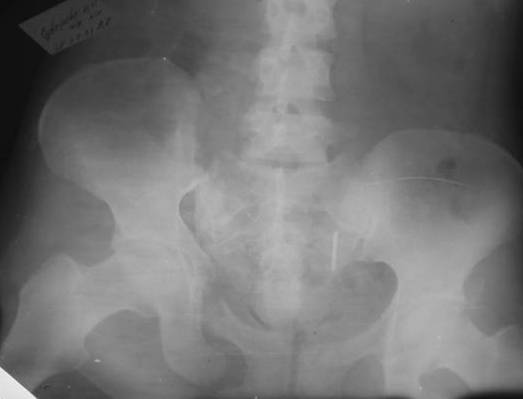

Дорогой Андрей. Мы имеем дело с комбинированной (ротационно и вертикально) нестабильностью таза со смещением правого гнемипелвиса. При таких переломах, фиксация только переднего полукольца вне зависимости от метода фиксации, как уже было сказано Djoldas Kuldjanov, M.D., не может создать адекватной фиксации. И перелом пластины был вполне ожидаемым после активизации пациента. Смещение сохраняется, и по-видимому не 2 см., а все 4, если не более. Разница всего (+2 см) по конечностям как вы указываете, скорее скомпенсировано позвоночником и протезом. Дополнительные снимки или КТ исследование помогли бы уточнить степень смещения с точностью до мм., выявить перелом поперечного отростка пятого поясничного позвонка, или помимо разрыва правого крестцово-подвздошного сочленения выявить перелом боковой массы крестца справа и т.д. При возможности, конечно, все это желательно сделать. Но мало что изменится с практической точки зрения, т.к. задача - это низведение репозиция и надежная фиксация правого гемипелвиса. Учитывая плачевный опыт стержневого аппарата, давность травмы совершенно очевидно, что поставленная задача достижима при открытой репозиции и одномоментной фиксации переднего полукольца с артродезированием правого крестцово-подвздошного сустава. Операция выполняется в положении больного на здоровом боку или полубоку из расширенного трансоссального подвздошно-пахового доступа с переходом на лонное сочленение доступом по Pfannenstiel. Указанный доступ обеспечивает подход к крестцово-подвздошному сочленению как спереди так и сзади. После артродезирования выполняется синтез лонного сочленения. Клинический пример

Пациентка С.26 лет. Травма за 6 месяцев до поступления

Укорочение правой нижней конечности до 10см

23.09.2003. Одновременный остеосинтез переднего и заднего тазовых полуколец

Результат через 10 дней

и 8месяцев после операции

> Результат через 10 дней и 8месяцев после операции

Да, забыл сказать - отличная работа, искренне восхищаюсь. Кость рубите по Judet (немного не разобрался по рисунку)?